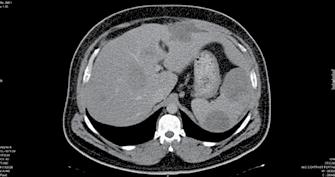

Caz rar de gastrită cu CMV imitând carcinomul gastric– prezentare de caz

As. Univ. Dr. Constantin Budin, As. Univ. Dr. Daniel Stăniloaie, Dr. Andreea Tănase, Dr. Alexandru Ilco, Dr. Tarek Ammar, Dr. Andrei Seceleanu, Dr. Raluca Petre, Dr. Anca Lăzăroiu, Dr. Diana Cîșleanu, Dr. Diana Iacob